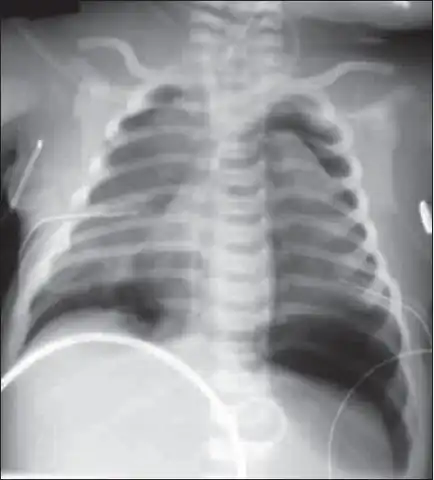

| X-ray showing lung damage in response to meconium in a newborn. | |

| Diagnostic method | Based on symptoms, confirmed by chest X-ray[1] |

In about 10% of cases babies pass meconium before delivery.[1] Risk factors include fetal distress, postterm pregnancy, and emergency cesarean section.[3] If this is subsequently breathed into the lungs it may result in inflammation of the lungs and blockage of airways.[1] Diagnosis is based on symptoms and a chest X-ray.[1]